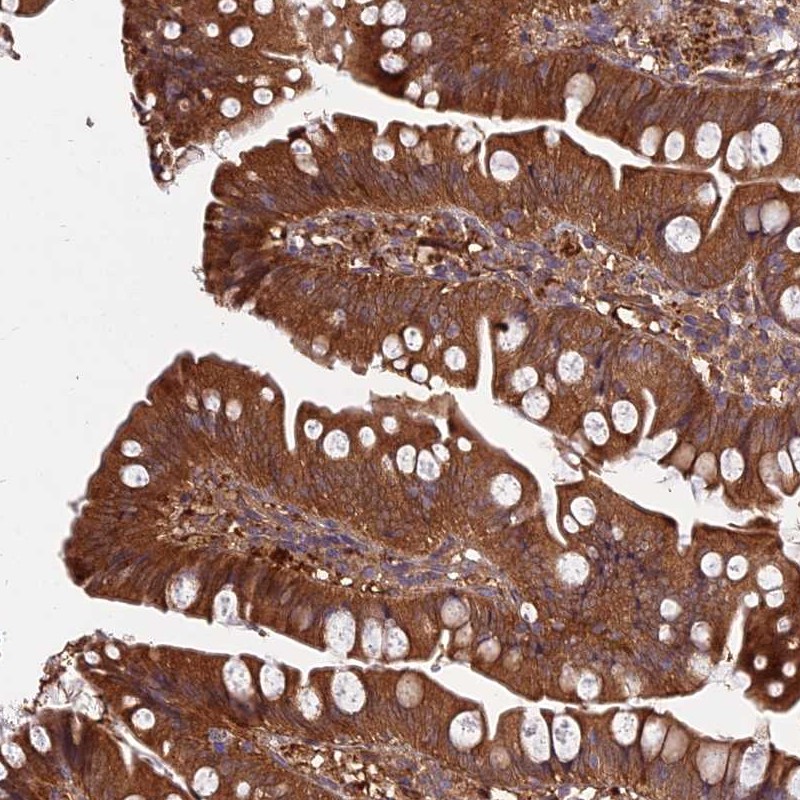

Immunohistochemical staining of human small intestine shows strong cytoplasmic positivity in glandular cells.